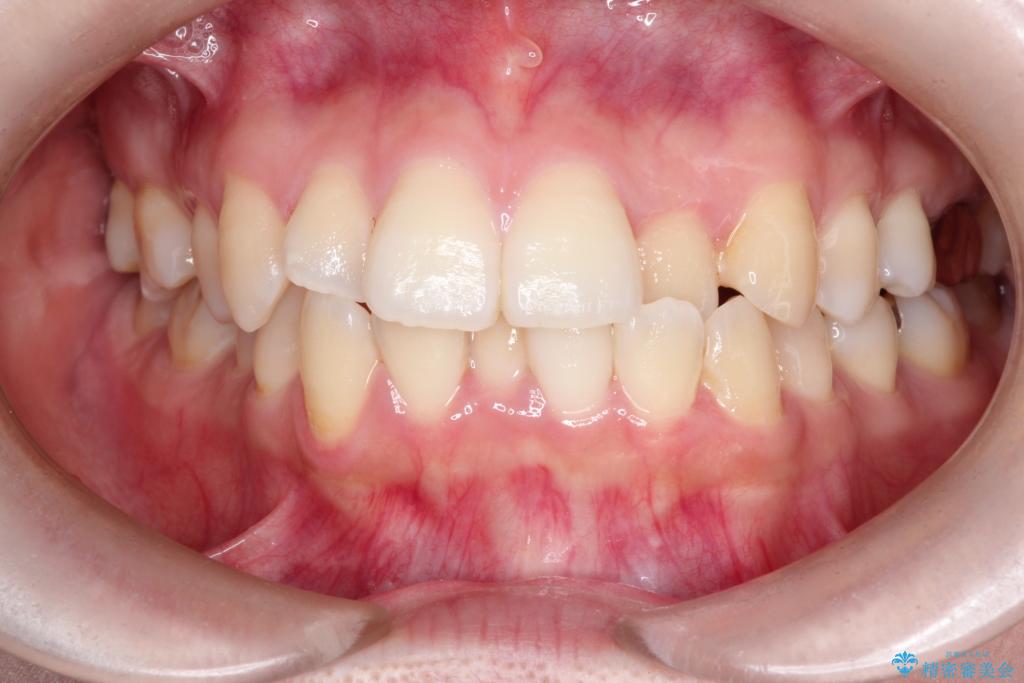

【ワイヤー矯正】口元を下げたい、下の歯の凹凸を無くしたい

- 主訴:口元を下げて前突感を無くしたい、下の歯の凹凸も無くしたい

骨格的顎の変位を認めたため、顔貌に対しピッタリ上下の歯の正中を合わせることは難しいと説明し、上下左右計4本小臼歯を抜歯しワイヤー矯正治療を行いました。